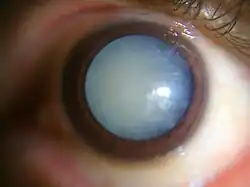

Nuclear sclerosis cataract of a 70-year-old male

Nuclear sclerosis cataract of a 70-year-old male -

Dense white mature cataract of a 60-year-old male

Dense white mature cataract of a 60-year-old male -